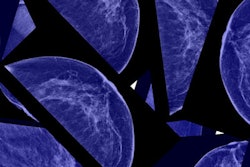

The clinical performance of radiologists improves when digital breast tomosynthesis (DBT) is combined with conventional 2D full-field digital mammography (FFDM) for breast cancer screening, according to research published in the September issue of Academic Radiology.

| Performance of DBT + FFDM vs. FFDM alone | ||

| FFDM | DBT + FFDM | |

| Recall rate | 8.2% | 5.4% |

| Cancer detection per 1,000 cases | 3.5 cancers | 5.4 cancers |

| Total invasive cancers found | 29 | 48 |

Of the 10,878 FFDM plus DBT cases interpreted, 588 (5.4%) were recalled, compared with 888 (8.2%) of the retrospective FFDM-only cases.

Overall cancer detection rates were 5.4 per 1,000 for the DBT plus FFDM interpretations and 3.5 per 1,000 for the FFDM-only interpretations. The cancer detection rate for all screened women who had FFDM only during this period that was interpreted by any radiologist in the practice was 2.9 per 1,000 screens, according to Rose and colleagues. Also, the FFDM-DBT combination found more invasive cancers than FFDM alone, at 48 versus 29.